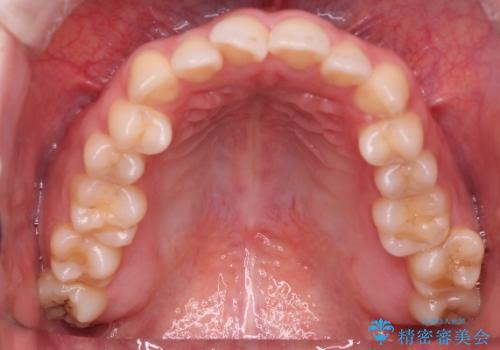

【オープンバイト】前歯のがたがたをなおしたい。

- 笑った時の前歯の見た目が気になることを主訴に来院されました。

上の歯が下の前歯を少し隠すぐらいを目指し、インビザラインにて治療を行いました。